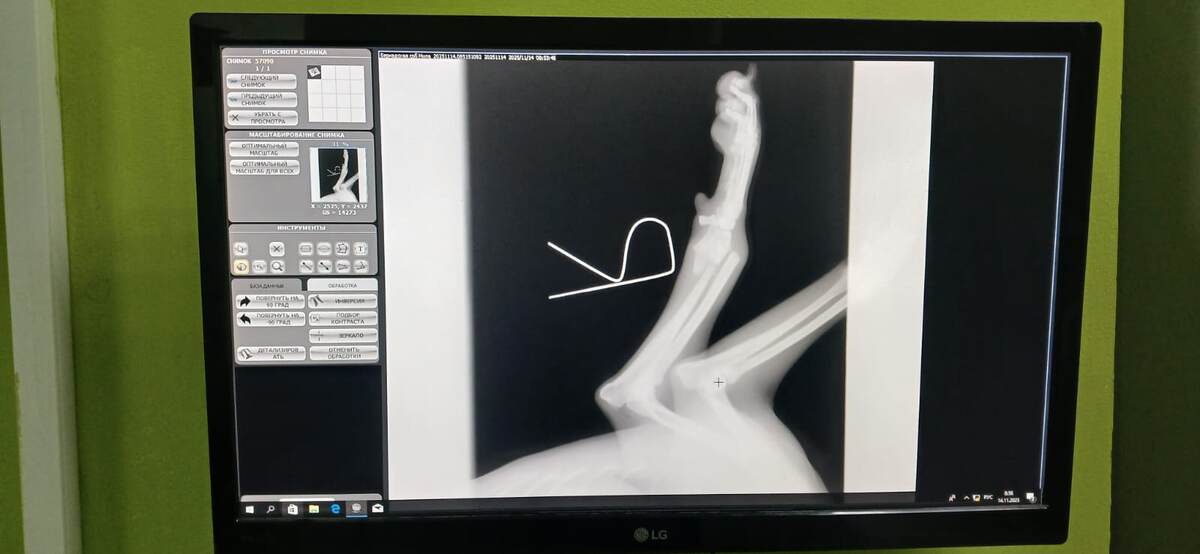

В нашем приюте случилось горе – к нам попала девочка со сломанной лапкой. Сердце каждого в команде сжалось от жалости, и мы немедленно отправились в ветеринарную клинику "Леопольд", надеясь на лучшее. К сожалению, прогнозы оказались неутешительными: лапа была сломана так, что животное не могло на нее опираться.

Точное время, которое девочка провела с травмой, оставалось неизвестным, но этот факт лишь усугублял ситуацию. Кость начала срастаться неправильно, и без вмешательства ветеринаров ситуация могла стать плачевной. Неправильно сросшаяся кость могла привести к дальнейшему повреждению и осложнениям.

Не теряя ни минуты, мы приняли решение об операции. Хирургическое вмешательство прошло успешно, и теперь наша маленькая подопечная проходит курс лечения. Несмотря на трудности, мы не сдаемся. Девочка очень неконтактная, и обработка ран, а также инъекции вызывают у нее стресс. Но мы делаем всё возможное, чтобы облегчить ее состояние и пройти этот непростой этап.